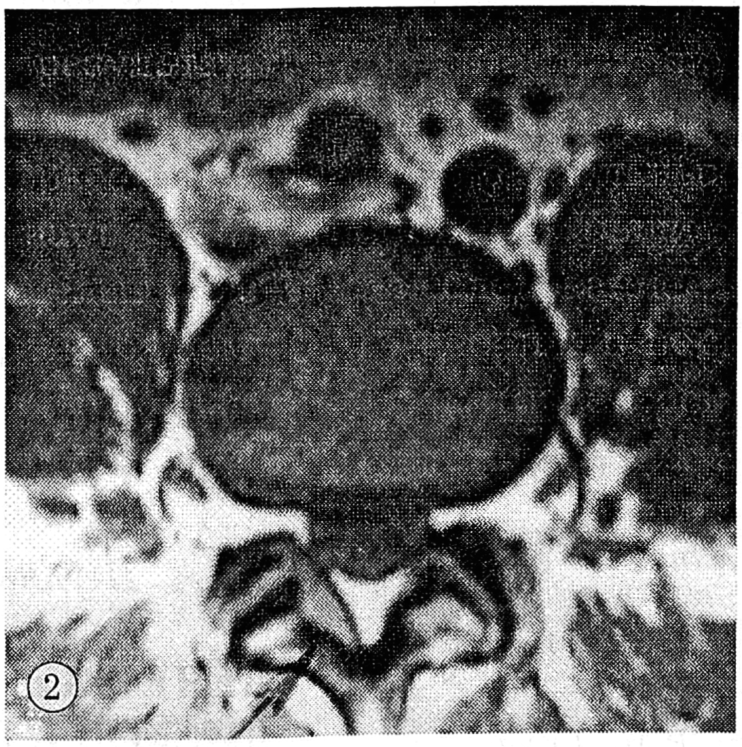

Установлено, что через 6—12 мес после физиотерапевтического лечения наступило значительное утолщение задней продольной связки над грыжевым выпячиванием при сохранении его начального размера (рис. 1). Утолщение задней продольной связки совпадало с усилением корешкового синдрома. Утолщение желтой связки также приводило к сужению позвоночного канала в зоне грыжевого выпячивания (рис. 2).

Рис. 2. Гипертрофия желтой связки (MP-томограмма, аксиальный срез).